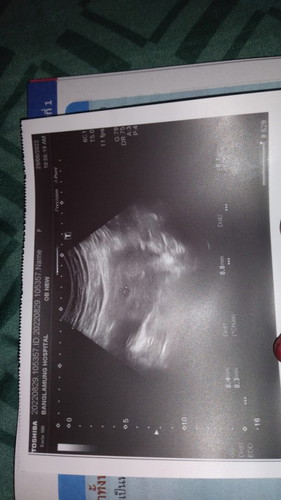

นับจากประจำเดือนวันแรกครั้งสุดท้ายได้6w6วัน แต่พอหมออัลตร้าซาวหน้าท้องบอก4-5w นี่ปกติไหมคะ แล้วมีคุณแม่ท่านไหนน้ำหนักเกิน90ตอนเริ่มท้องไหมคะ #ท้องแรก #ขอบคุณสำหรับคำตอบค่ะ #ขอคำแนะนำหน่อยค่ะ

หนัก 95 ค่ะ ตอนตรวจเจอว่าท้อง เราไปหาหมอเลยค่ะ ถ้านับตามประจำเดือนรอบล่าสุด หมอบอกประมาณ 6 วีค เรามีเลือดออก ไปซาวด์ผ่านทั้งหน้าท้อง และช่องคลอด ไม่เจออะไรเลยค่ะ คุณหมอนัดห่างไปอีก 2 อาทิตย์ ซาวด์ใหม่ผ่านช่องคลอด เจอแค่ถุงการตั้งครรภ์ นัดห่างอีก 2 อาทิตย์ ซาวด์ผ่านช่องคลอด รอบนี้เจอตัวน้องขนาด 2 เซน กับหัวใจเต้น เครื่องคำนวนให้ได้แค่ 8 วีค กับอีก 3 วันค่ะ มันน่าจะมีสิทธิ์คลาดเคลื่อนได้นะคะแม่ เราก็เป็น ☺️

ถุงตั้งครรภ์เล็กอยู่เลยค่า น่าจะไข่ตกช้าค่ะแม่ ยึดตามหมอเลยค่า